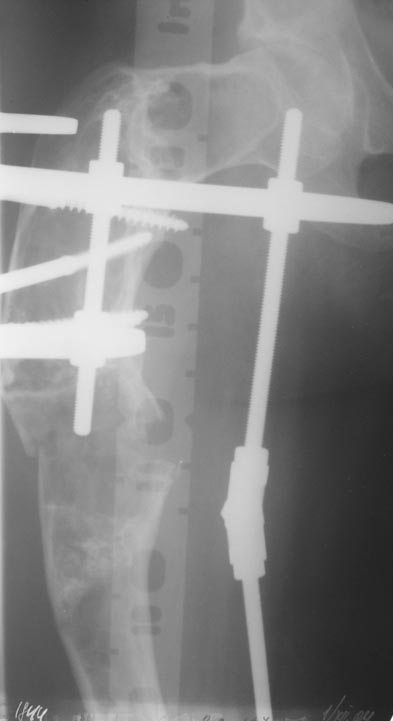

Leonid Pollyak 27 Ноябрь 2004, 11:17

Уважаемые коллеги! Большое спасибо за живой отклик и предложения по тактике лечения. Больной произведен первый этап - стержневой аппарат издвух баз, кортикотомия, остеоклазия и начата коррекция в аппарате. Почти исправлен угол, не сегодня укорочение 2см. Когда завершим коррекция, представлю рентгенограммы.

Операция выполнялась с помощью А.Н.Челнокова. Очень понравилась технология выполнения блокируемого остеосинтеза с использованием спицевого дистрактора, модифицированный гвоздь с латерализованным проксимальным отделом и возможностью многовинтовой фиксации проксимального и дистального участков бедра.